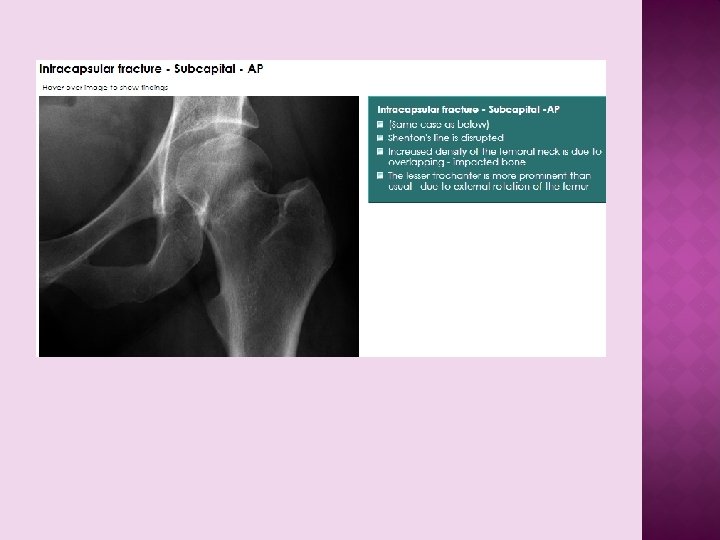

RADIOLOGICAL FX Osteoporotic bones